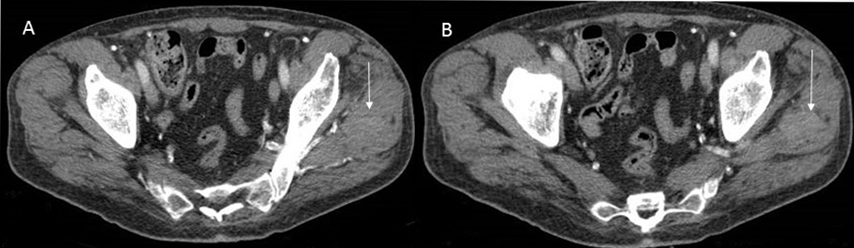

We report a case of a 64-year-old non-smoking male, who had had intermittent exposure to asbestos for three years. He had been undergoing treatment for hypertension. He presented with dyspnea on moderate exertion that had developed over several days, discomfort in the left hemithorax, and some intolerance to decubitus positions. The patient had a weight loss 10 kg in the last three months. A physical examination showed that he was conscious and lucid with normal coloring. Respiratory auscultation revealed hypophonesis in the lower half of the left hemithorax and right basal hemithorax. Hematological and hepatic findings were within the normal range. Tumor markers carbohydrate antigen (CA) 125, carcinoembryonic antigen (CEA), alpha-fetoprotein (AFP), CA 15-3, and CA 19-9 were shown to be within the normal range. Simple radiography of the posterior-anterior thorax showed bilateral pleural effusion with multiple nodular images in both hemithoraces (Figure 1). A contrast computed tomography (CT) scan of the thorax and abdomen revealed multiple bilateral pulmonary and pleural lesions, mediastinal lymphadenopathies (Figure 2), intra-abdominal implants (Figure 3), and a 56×40 mm polylobulated mass in the left buttock (Figure 4). A biopsy of the mass in the left buttock was made with an 18-gauge needle. Pathological study involved obtaining three cores of tissue measuring between 0.7 and 1 cm in length that were fixed in formalin. In the histological sections, we observed connective tissue infiltrated by epithelioid cells arranged in nests and trabeculae that showed atypia with hyperchromatic nuclei and prominent nucleoli. Occasional non-atypical mitosis was also detected (Figure 5). Immunohistochemical study revealed cytoplasmic positivity for keratins 5/6 and 7. Nuclear and cytoplasmic positivity was observed for calretinin, while nuclear positivity was detected for Wilms tumor 1 protein (Figure 6). Negative results were found for epithelial membrane antigen (Ber-Ep4), thyroid transcription factor-1 (TTF-1), protein suppressor p63, keratin 20, CEA, prostate-specific antigen (PSA), renal cell carcinoma (RCC), vimentin, common lymphoblastic leukemia antigen (CD10), S-100 protein, and CA 19.9. These results confirmed the diagnosis of metastasis of epithelioid mesothelioma. The patient passed away eight days later.

Figure 4: (A, B) Contrast computed tomography scan. In the pelvic sections, a solid mass measured with a soft tissue attenuation coefficient and oval morphology measuring 57×40 mm was observed in the left mid buttock muscle.